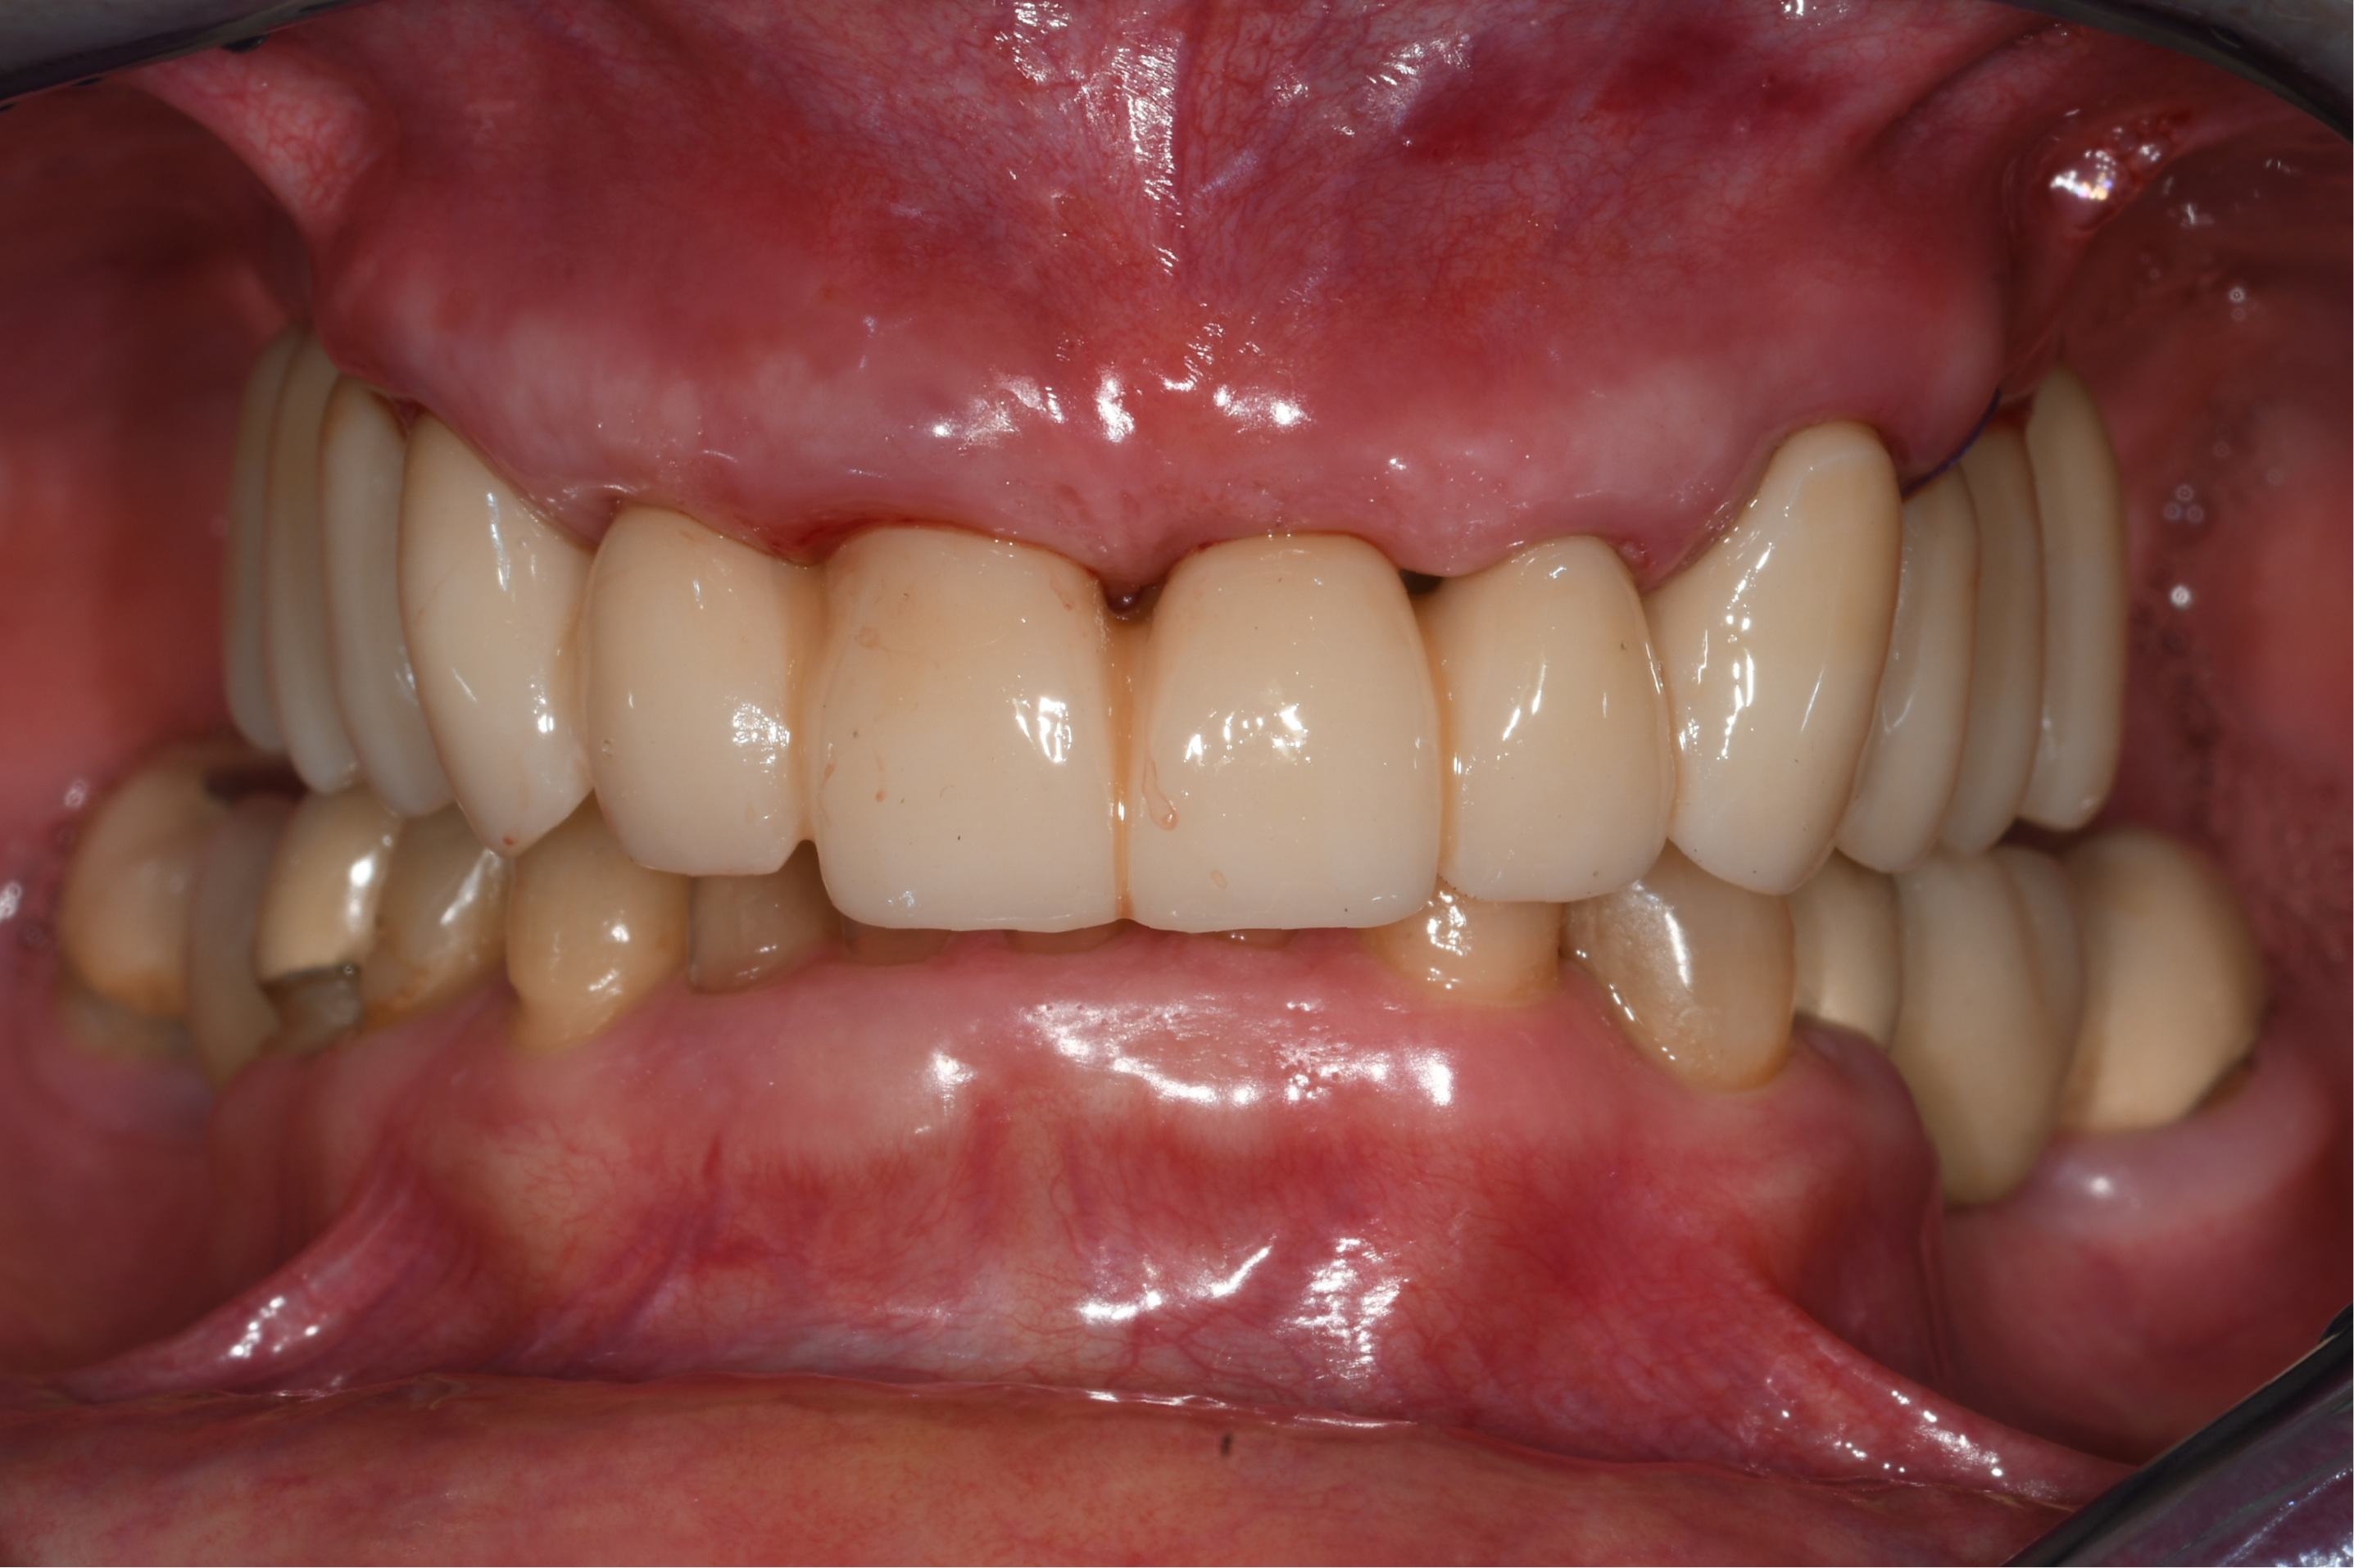

The photogrammetric dataset was transferred to the dental laboratory, enabling same-day fabrication of a milled long-term provisional. The provisional restoration was seated on the afternoon of surgery, restoring aesthetics and function immediately.

Healing Phase and Prosthetic Release

Healing progressed without complications. Stable peri-implant soft tissues and successful osseointegration were observed. After removal of the provisional restoration, a second intraoral photogrammetry scan was performed to document the implant positions at the time of prosthetic release. These data were transferred to the patient’s general dentist for final restoration fabrication.